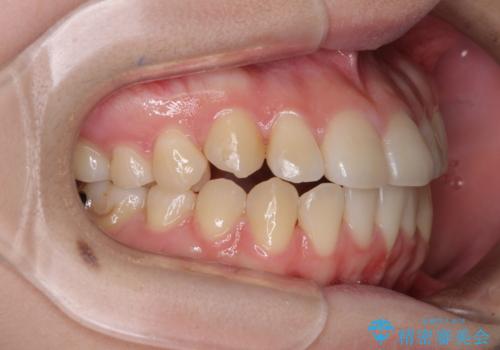

カリエール・ディスタライザーとインビザラインを用いた八重歯の改善

- 前歯の叢生と上顎左右の八重歯を気にして来院された患者様です。

奥歯の咬み合わせを見ると、左側は上顎が下顎に対して相対的に前方にあり、上下の前歯が接触していない状態でした。

咬み合わせを改善するためには、左側上顎臼歯を後方に移動させた咬み合わせにする必要があります。

インビザライン単体で改善することも可能性もありますが、インビザライン単体で達成する可能性が低いと考えられたため、カリエール・ディスタライザーという補助装置を併用して、より確実性を上げることとしました。

奥歯の咬み合わせを改善しながら、並行してインビザラインで歯列を整えることとしました。

カリエールディスタライザーを併用したことで、左側臼歯の咬み合わせを確実に改善させることができました。